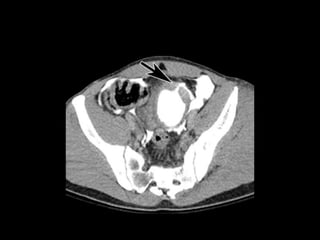

TRAUMA VESICAL

• 22% Trauma urologico

• Traumatismos cerrados representan 67% y el

86%

• 70-90% asociacion con fractura pelvica

• Trauma penetrante 14-33%

• Iatrogenos 3-4%

Extraperitoneal

Intraperitoneal

• Estudio elección: cistograma de llenado 350-

400ml solución salina, con 4% de contraste a

una altura de infusión de 40 cm.